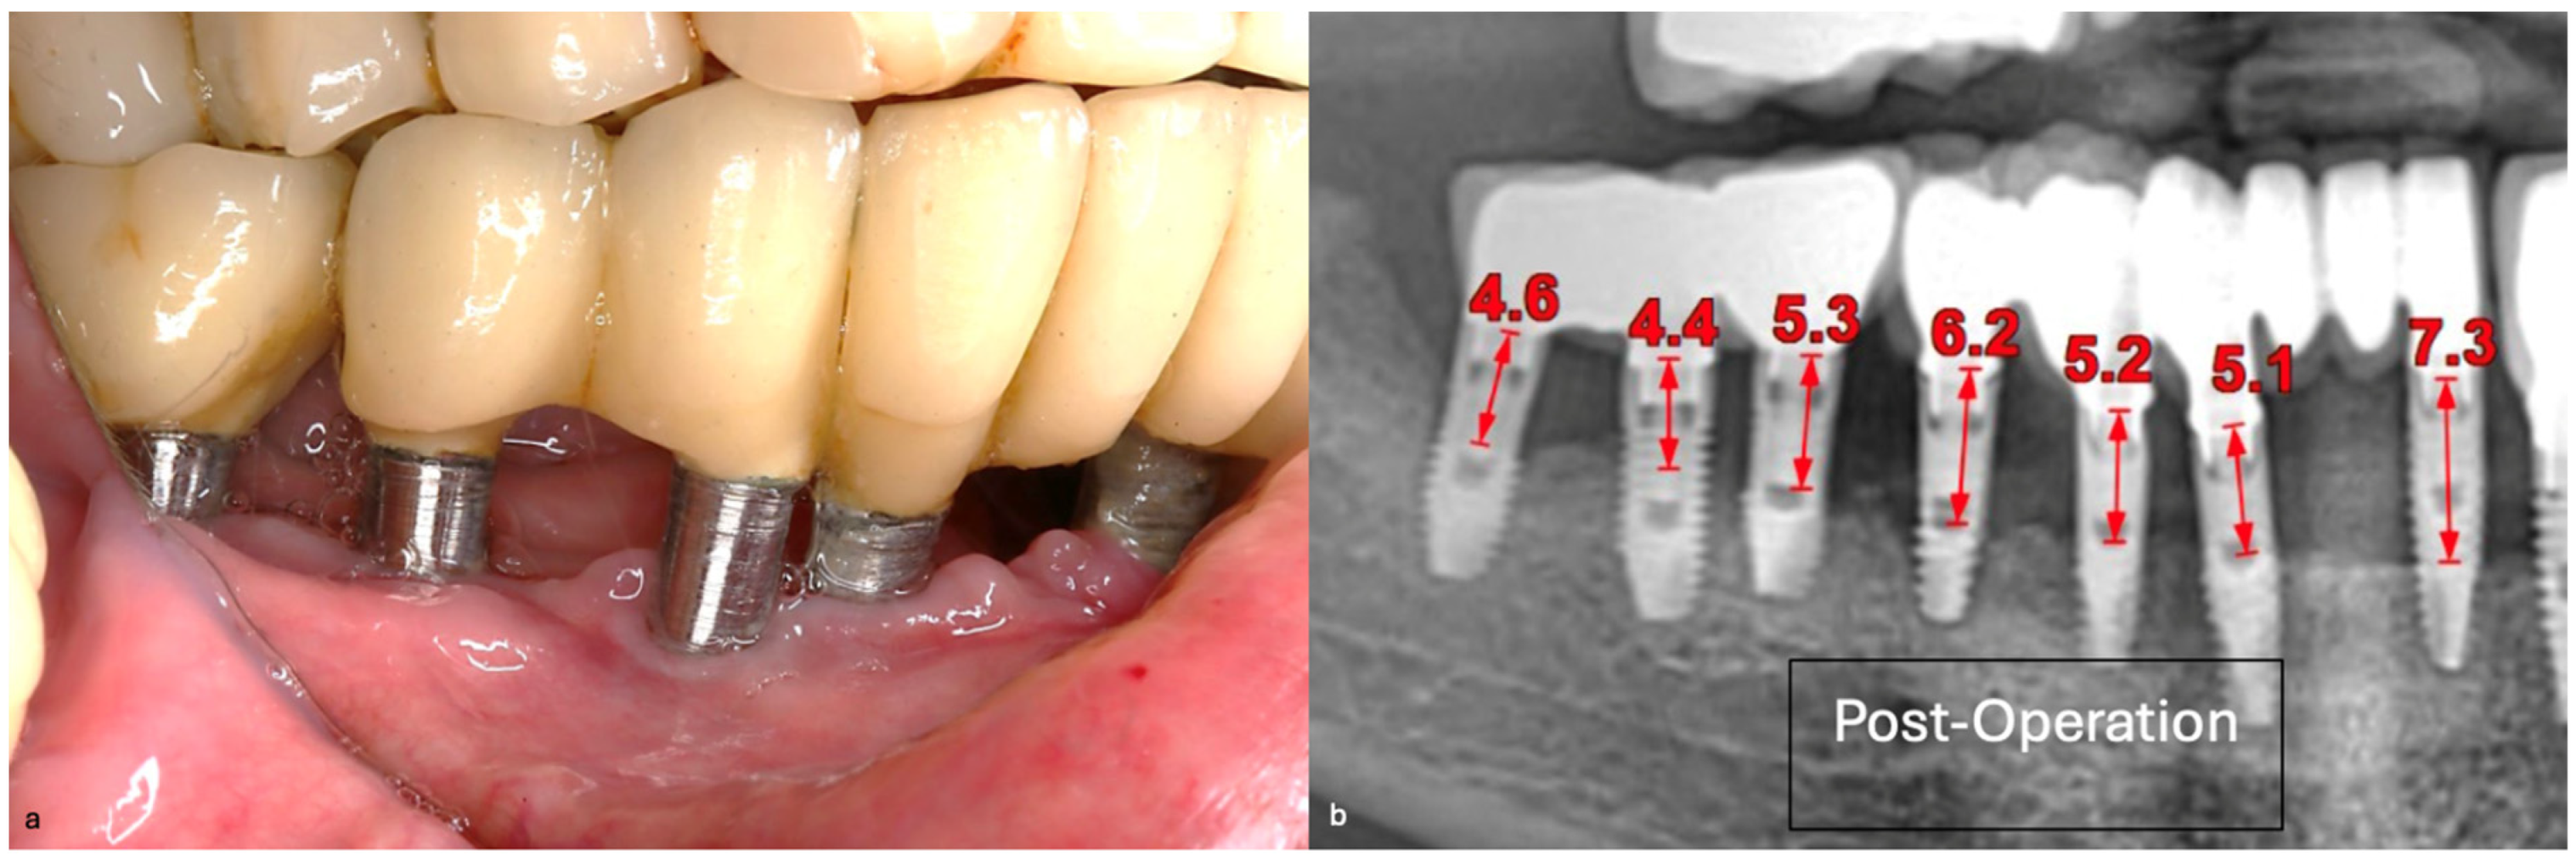

The intraoral examination revealed poor oral hygiene, characterized by significant plaque accumulation (over 65% plaque index) along the gingival margins and interdental areas. The periodontal status evidenced a progressive periodontal disease, with bleeding on probing (BoP) over 60%, mainly around all dental implants; peri-implant tissues possessed a high level of inflammatory condition, with localized swelling, high level of BoP, redness, and suppuration at the site of teeth #46 and #47, indicating local acute inflammation. The probing depth (PD) at site implant #46 exceeded 9 mm at both the mesial and distal sites, and at #47, the mesial site had a PD of 7.8mm, while the distal site showed lower bone loss (Figure 7).

Radiographically (Figure 8), the findings demonstrated full mouth edentulism, rehabilitated with upper and lower bridges and crowns supported by dental implants, as well as bone loss at #37, #46, and #47. The peri-apical radiograph (Figure 7) showed two dental implants, each measuring 13 mm, with bone loss around implant #46 (exceeding 60% of the implant length) and around implant #47 (exceeding 70% of the implant length).

The patient was provided with postoperative care instructions, including continuing with Moxypen 500 mg (Teva Pharmaceuticals, Petah Tikva, Israel) taken three times per day for three days, in addition to the medication previously prescribed. Follow-up appointments to monitor healing and treatment efficacy. The prosthesis adaptation to the gingiva was followed up for three months, when tissue healing was complete, and the need for readapting the prosthesis was evaluated. Considerations for readaptation included facilitating patient cleaning procedures. The patient was advised to enhance oral hygiene practices and scheduled for follow-up appointments. At the 14-month follow-up, the patient exhibited significant clinical improvements, with reduced PDs and evidence of bone regeneration around the affected implants (Figure 14). Notably, despite suboptimal oral hygiene practices being observed after 46 months, the patient maintained stable peri-implant conditions with minimal signs of mucositis, as evidenced by probing depths of 2 mm at implant #46 and 1 mm at implant #47, revealing significant improvements. This outcome underscores the potential durability of the surgical and regenerative interventions employed. However, it also highlights the critical importance of patient compliance with oral hygiene and regular maintenance visits in sustaining treatment outcomes, emphasizing the need for ongoing supportive peri-implant therapy. These findings suggest sustained peri-implant health over the long term. At the last follow-up, the patient reported being comfortable with the prosthesis and experiencing ease of cleaning. The intraoral X-rays indicated vertical bone gains of 7.5 mm around implant #46 and 8 mm around implant #47. Similar results were found after 43 months (Figure 14 and Figure 15), demonstrating the success of the treatment.

Figure 14. Periapical images showing the evolution of the case (red arrows show the distance from the implant platform to the bone—(A) Baseline; (B) After 14 months; (C) After 43 months).